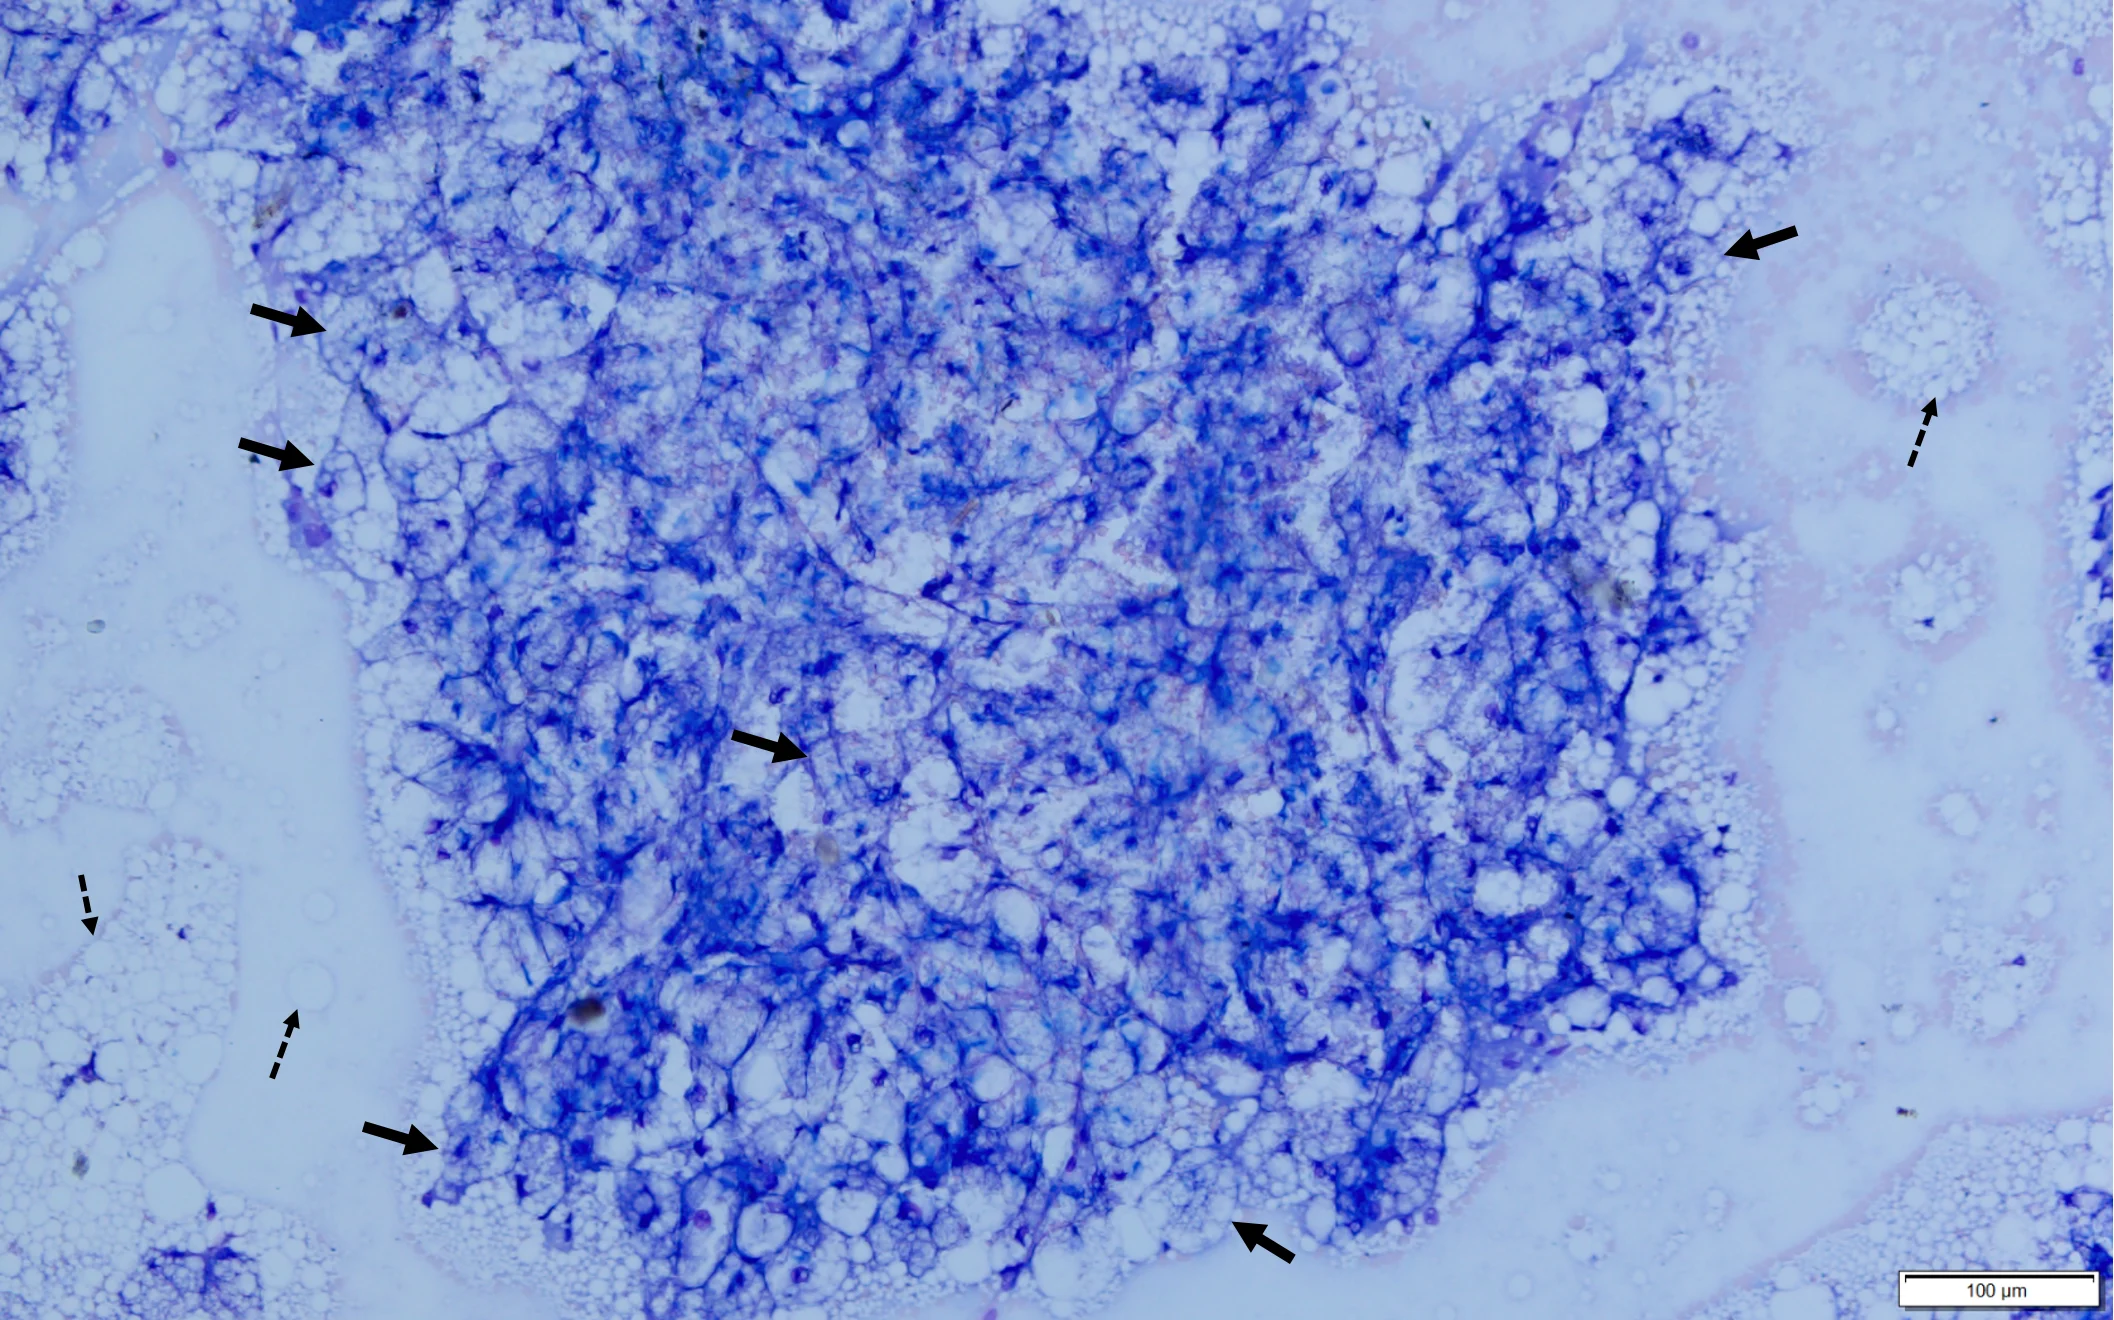

Abdominal ultrasonography revealed an enlarged liver with rounding of the caudal ventral margin. The hepatic parenchyma was hyperechoic and hyperattenuating, suggestive of lipid deposition. A fine-needle aspirate of the liver revealed abundant hepatocytes with marked vacuolation consistent with lipid (Figures 1 and 2).

Fine-needle aspirate from the liver of a cat. A cohesive sheet of numerous hepatocytes (solid arrows) can be seen. Cytoplasm of almost all hepatocytes is markedly distended with large (ie, macrovesicular) and small (ie, microvesicular) clear vacuoles that often obscure the nucleus and make observation of hepatocytes difficult. Numerous free lipid droplets are present in the background (dashed arrows). Modified Wright’s stain, 200× magnification